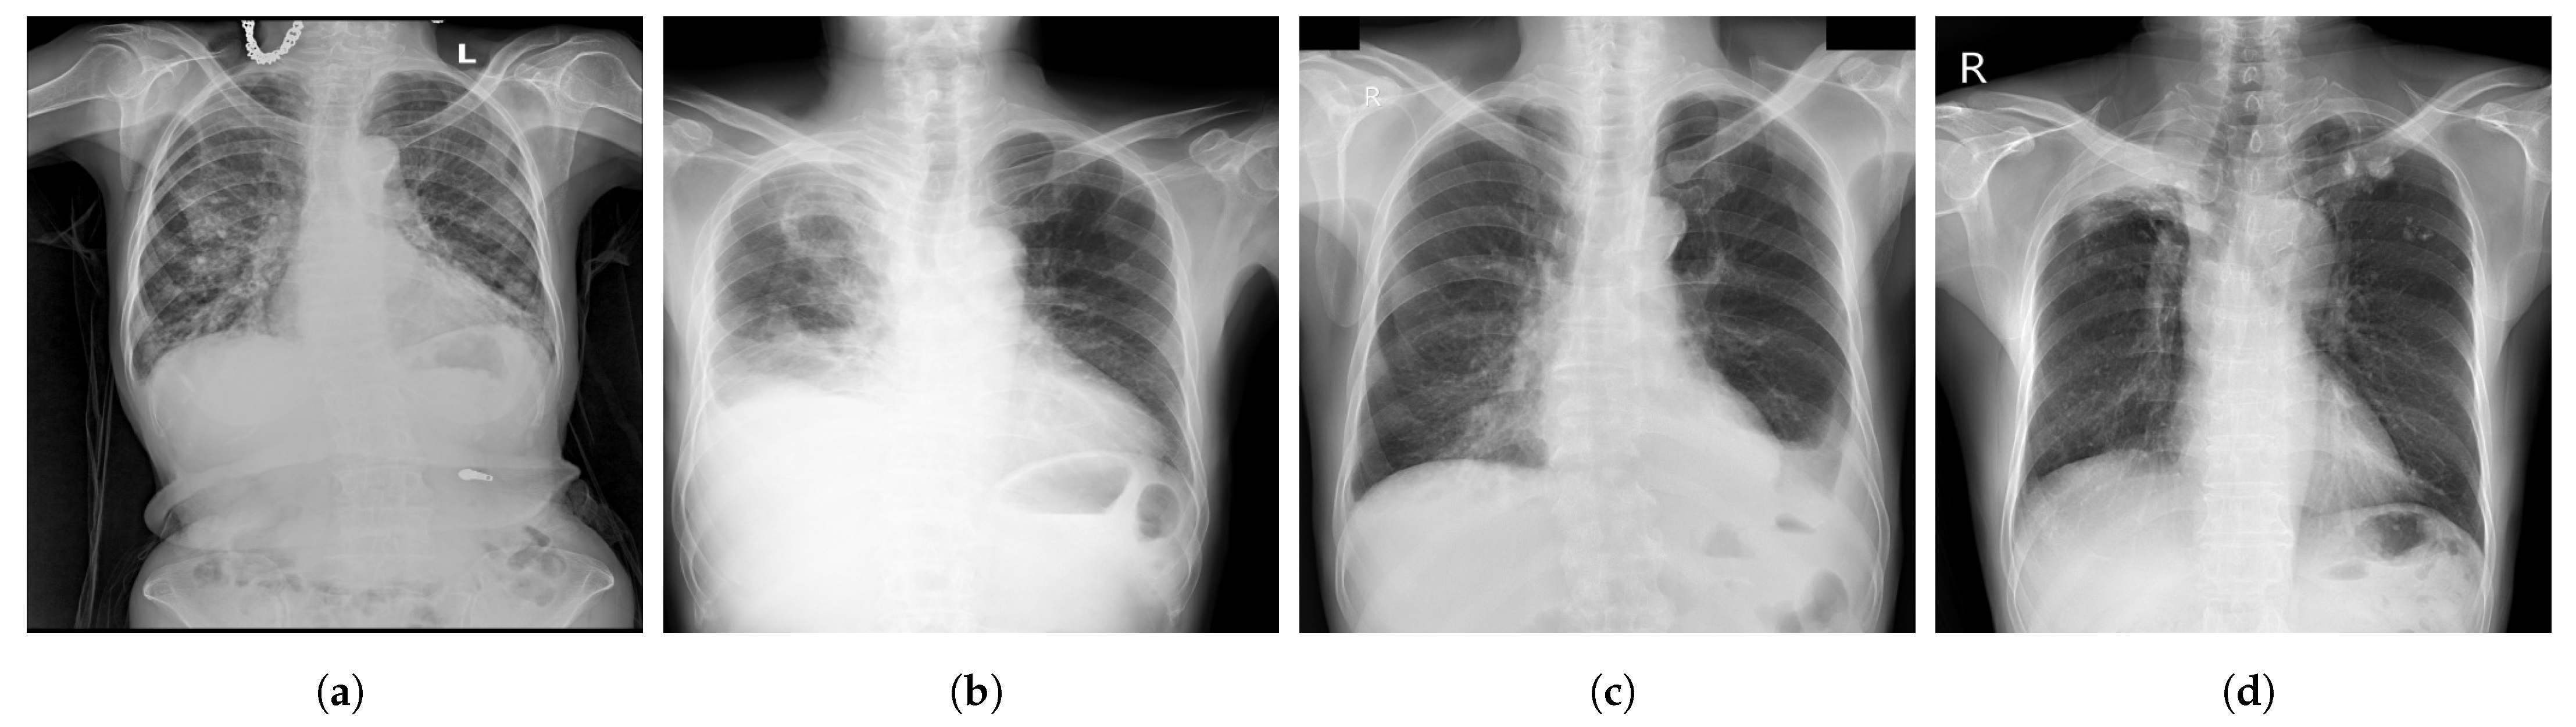

- ChestX-ray14 [39] is a dataset of images extracted from the PACS (Picture Archiving and Communication Systems) databases. It is an upgraded version of ChestX-ray8 dataset with six more common chest abnormalities (hernia, fibrosis, pleural thickening, consolidation, emphysema, and edema). ChestX-ray14 has 112,120 frontal view CXR images (51,708 images contain one or multiple abnormalities and the remaining 60,412 images do not include any of the 14 abnormalities) belonging to 30,805 unique patients. ChestX-ray14 was also labeled using NLP techniques. Examples of CXR images from ChestX-ray14 are depicted in Figure 2.

Figure 2.

Examples of CXR images from ChestX-ray14 dataset [39] where, (a) Nodule; (b) Emphysema; (c) Effusion; (d) Infiltration.